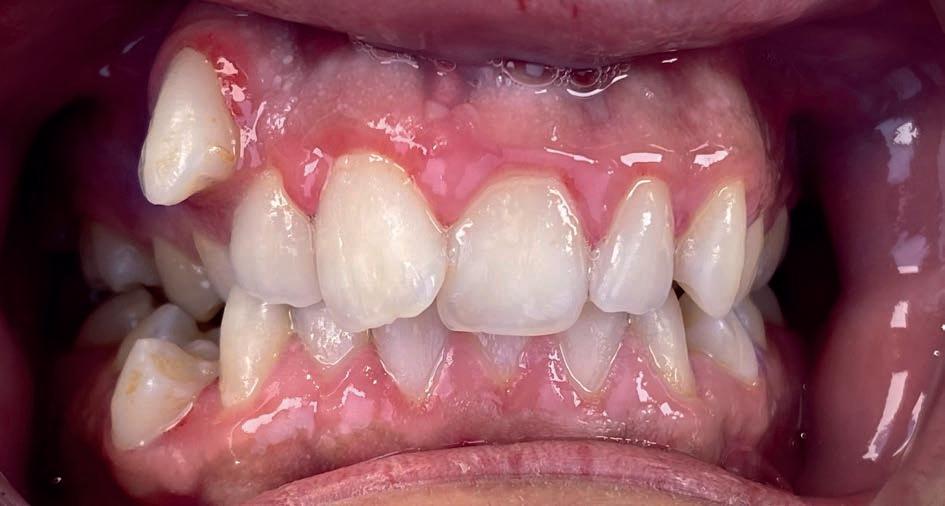

Casus in Proces

Patiënt Sonnie presenteerde zich met ernstig ruimtegebrek ter hoogte van de 13 en 44 en een kruisbeet aan de zijde van de 15 en 14. De 13 was ectostematisch gepositioneerd, waardoor extractie aanvankelijk als mogelijke behandeloptie werd overwogen.

Door een combinatie van verbreding en het inzetten van een D-gainer wordt de benodigde ruimte gecreeerd om alle elementen correct in de tandboog te positioneren, waardoor extracties kunnen worden vermeden. De behandeling zal binnen twee jaar worden afgerond; het eindresultaat wordt gedeeld in editie 2 van ons magazine.

Midden behandeling